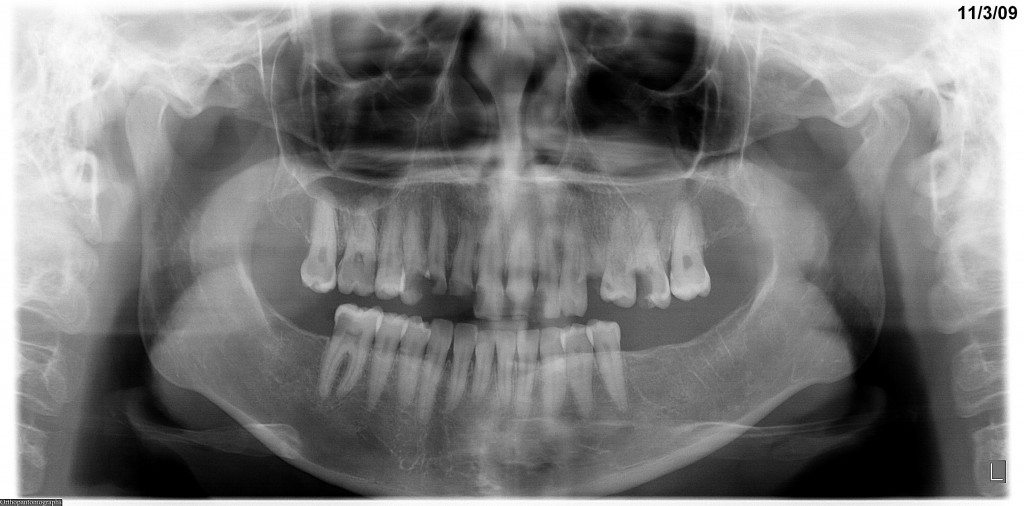

Smile Design & Wellness Center is proud to be one of the first practices in Brevard County to have digital X-rays. Digital X-rays have many advantages over conventional X-rays. Most importantly they are significantly less in radiation, estimates are as high as 90% but probably more like 75% less than conventional.

We are pleased to add to our Digital X-ray technology a Vatech Cone Beam CT X-ray (CBCT). This is a 3 dimensional X-ray that is very low in radiation but high in diagnostic value. It is very useful in implant planning and surgery and in many other situations. Click on the link below to learn more about our Digital X- Rays.

Digital X-rays can be enhanced and magnified and are easily seen by the patient to help understand their diagnosis and conditions. The digital panoramic X-ray shows structures not seen with small X-rays, such as the sinuses, the jaw joints, impacted wisdom teeth and many other conditions. Digital X-rays are also very easy to transfer to specialists or other dentists. We tailor the need for X-rays to each condition and patient. Many of our healthy patients are having X-rays only every two years.

Cone Beam X-rays are a 3 dimensional X-ray of the structures of the mouth. It is similar to a cat scan but fortunately is much lower (25 to 40 times lower) in radiation then a CAT scan. The Cone Beam X-ray is useful in evaluating the amount and quality of bone for dental implants. The software of CEREC is interfacing with cone beam X-ray software and enabling the planning and coordination of implant placement with the position of the final crown and fabrication of the abutment. View the Journal Article that Dr Edwards was a co-author in that showcased Cone Beam X-rays.